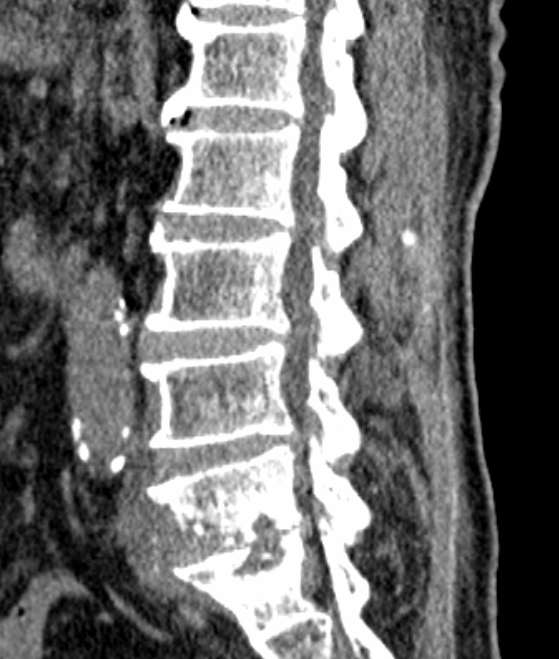

术前CT